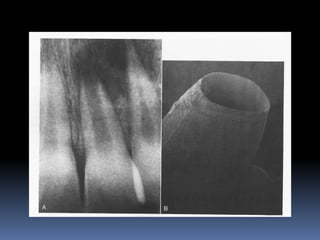

APEXIFICATION

Induction of a calcific barrier or creation of an artificial barrier

across an open apex

Technique:

Local anesthesia and Rubber Dam isolation

Access cavity preparation and extirpation of the pulp

Working length is established slightly short of the apex [to

prevent injury to apical tissues]

Instrumentation and copius irrigation

Drying the canal and introducing MTA into the canal

 Packing MTA using endodontic pluggers or special

system like MAP SYSTEM [Micro Apical placement]

 MTA acts as an artificial barrier against which Gutta

percha can be condensed.

 Calcium hydroxide produces a biologic barrier but takes

longer time.

APEXIFICATION Induction of acalcific barrier or creation of an artificial barrier across an open apex Technique: Local anesthesia and Rubber Dam isolation Access cavity preparation and extirpation of the pulp Working length is established slightly short of the apex [to prevent injury to apical tissues] Instrumentation and copius irrigation Drying the canal and introducing MTA into the canal

 Packing MTAusing endodontic pluggers or special system like MAP SYSTEM [Micro Apical placement]  MTA acts as an artificial barrier against which Gutta percha can be condensed.  Calcium hydroxide produces a biologic barrier but takes longer time.